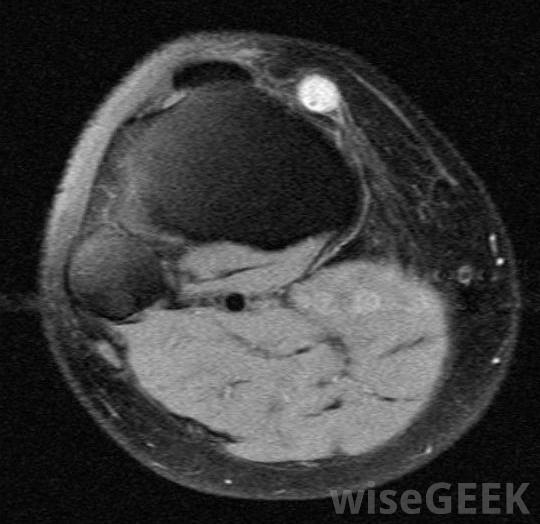

腕掌侧凸是由于外伤、劳损或先天性疾病在手腕顶部形成的骨质肿块。在某些患者中,它可能是良性的,除非它生长或开始引起问题,否则不需要任何行动。其他患者需要治疗来解决疼痛、酸痛,在许多情况下,如果保守治疗不能有效的话,"/要密切注意受累的手腕,尽早发现复发的迹象。有些患者出生时有腕掌骨肥大,而有些患者在中年时出现这种症状。肿胀可能出现在手腕上,掌骨关节的地方。这应该摸起来很硬,而且可能因为炎症而发热。这种情况有时会与神经节囊肿混淆,因此必须进行彻底的评估,以确定手腕上部肿胀的原因当然,患者的诊断是正确的。神经节囊肿可能会在腕掌骨旁形成创伤史可以作为一个潜在的指标,重复性压力也可以关节周围的慢性炎症可能会导致骨刺的形成,随着时间的推移,腕掌侧隆凸的基本治疗方法可以包括消炎药来减轻肿胀和阻止生长。夹板和适当的支撑也可以帮助,尤其是当重复性劳损是罪魁祸首时,那些继续经历疼痛和僵硬的患者可以讨论更具攻击性的选择。在大多数情况下,医生只会建议积极治疗在其他方法无法缓解不适和行动不便后。在手术中,护理人员可以去除骨刺并抚平周围的骨头,以阻止这种情况的复发在腕掌骨旁形成一个神经节囊肿,在这种情况下,它也需要切除。在愈合过程中,病人可以戴上支撑关节和促进康复的支架。一旦医生认为安全,就可以移除这些支架。定期检查以确定骨刺是否正在恢复生长,这是可以的在某些情况下,这是一个值得关注的问题。在腕掌侧弯的愈合过程中,患者可能会佩戴牙套来支撑腕部区域并促进康复有腕掌侧弯病史的人可能需要密切关注受影响的腕关节,尽早发现复发的迹象。如果医生不能清除所有的生长,或者没有充分剃掉周围的骨头,手术可能会失败。药物也可能无法抑制骨刺的复发,尤其是当患者停止服用或不定期服用时,可以通过影像学研究来追踪随时间推移的腕掌侧肌群,以便医生确定可能引起关注的变化。神经节囊肿的横切面,可发生在腕掌骨旁重复性压力可能导致腕掌侧肌群。